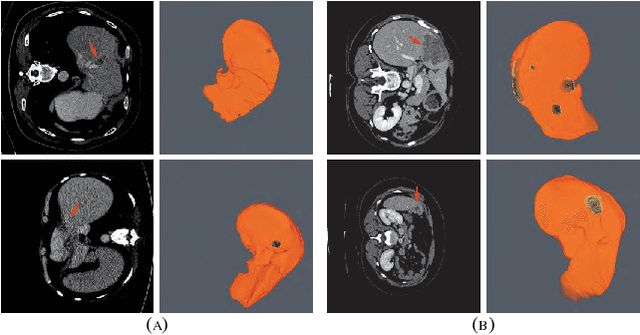

Abstract:The insufficiency of annotated medical imaging scans for cancer makes it challenging to train and validate data-hungry deep learning models in precision oncology. We propose a new richer generative adversarial network for free-form 3D tumor/lesion synthesis in computed tomography (CT) images. The network is composed of a new richer convolutional feature enhanced dilated-gated generator (RicherDG) and a hybrid loss function. The RicherDG has dilated-gated convolution layers to enable tumor-painting and to enlarge perceptive fields; and it has a novel richer convolutional feature association branch to recover multi-scale convolutional features especially from uncertain boundaries between tumor and surrounding healthy tissues. The hybrid loss function, which consists of a diverse range of losses, is designed to aggregate complementary information to improve optimization. We perform a comprehensive evaluation of the synthesis results on a wide range of public CT image datasets covering the liver, kidney tumors, and lung nodules. The qualitative and quantitative evaluations and ablation study demonstrated improved synthesizing results over advanced tumor synthesis methods.